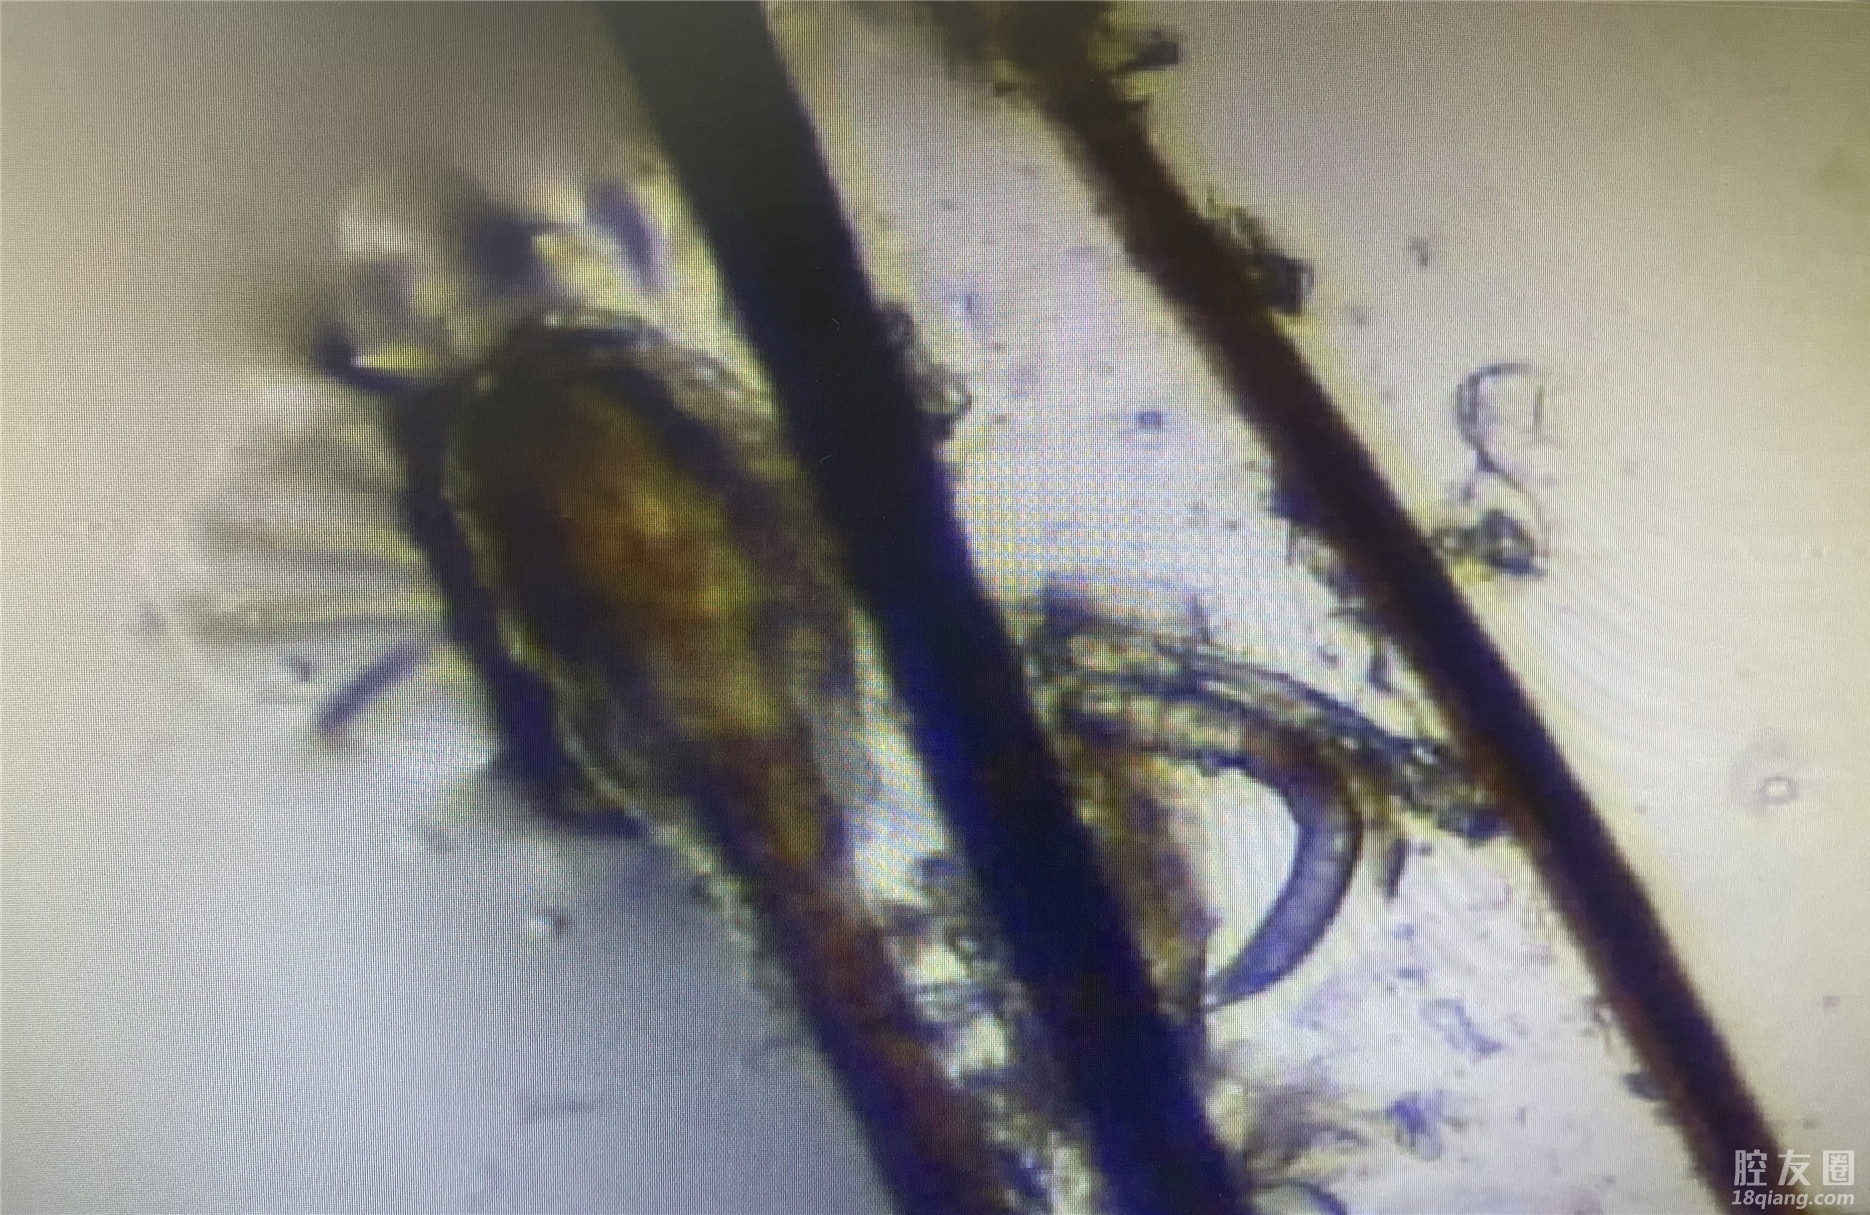

为了进一步验证猜想,张主任从王阿姨上下睑分别拔下3根睫毛,共12根睫毛进行检查。果不其然,通过检查,发现其睫毛根部存在大量的蠕形螨,且每一根睫毛无一幸免,甚至有些蠕形螨已经“抱团”!